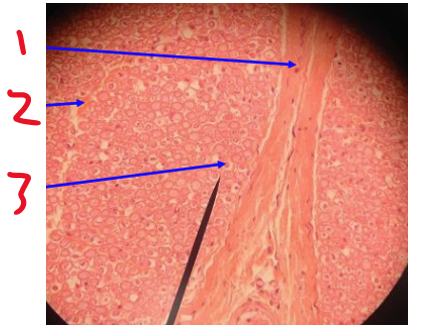

Name 1 (outer layer)

epineurium

Name 2

perineurium

Name 3

nerve fascicle

What is this a cross section of?

nerve